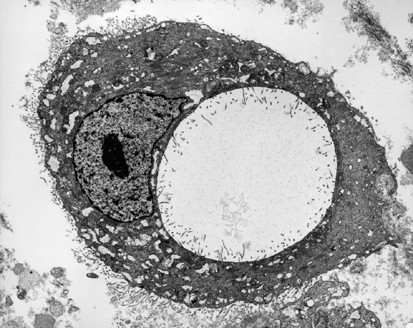

The most common ultrastructural characteristics of the mesotheliomas were the presence of long, slender, often branching, undulating microvilli on the apical surface of the cuboidal cells lining the tubules or papillae (Figure 3a, b), dilated intercellular spaces (Figures 3a and 4), and intracellular lumens (Figures 5 and 6). On occasion, a profusion of microvilli was also seen on the basal surface of the cells (Figure 7a) or involving the entire cell membrane (Figure 7b). The cytoplasm usually exhibited large amounts of intermediate filaments often arranged in bundles (Figure 8). A variable amount of glycogen was also a common finding (Figure 6). A rare cell exhibiting a single cilium was identified in three of the cases, and, in one of these, the cilium was intracytoplasmic (Figure 9).

In all of the cases in which electron microscopy studies were performed, this technique allowed the differential diagnosis to be clearly established between epithelioid mesothelioma and serous carcinoma. The mesotheliomas were characterized by a profusion of long, slender, wavy microvilli occurring along any of the surfaces of the cells. This is in contrast to the serous carcinomas in which the microvilli were less numerous, and straight, and, although they were of varying lengths, they were in general shorter and confined to the luminal and papillary surfaces. Additionally, the cell membranes in the serous carcinomas were intimately apposed, while, in the mesotheliomas, intercellular gaps that often exhibited microvilli were a common finding. Similar to previous ultrastructural studies, large collections of intermediate filaments arranged in tonofibrillar bundles and intracytoplasmic lumens covered by microvilli were common findings in mesotheliomas,65, 66, 67 but not in serous carcinomas.68, 69, 70 No intracytoplasmic lumens were identified in any of the serous carcinomas investigated, and only rare small bundles of intermediate filaments were found in a few cases. Another finding that was helpful in distinguishing serous carcinomas from mesotheliomas was the presence of multiciliated cells in serous carcinomas, but not in mesotheliomas. Multiciliated cells, such as those shown in Figure 10a and b, have previously been reported in serous carcinomas and are more often found in low-grade serous carcinomas and serous tumors of borderline malignancy originating in the ovary and peritoneum.23, 24, 69, 70, 71, 72 Neither in the present study nor in previous investigations have these cells been found in mesotheliomas. Cells presenting a solitary cilium or a few cilia have frequently been found in serous carcinomas, including those of high-grade malignancy; however, their occurrence in mesotheliomas is exceedingly rare.73, 74